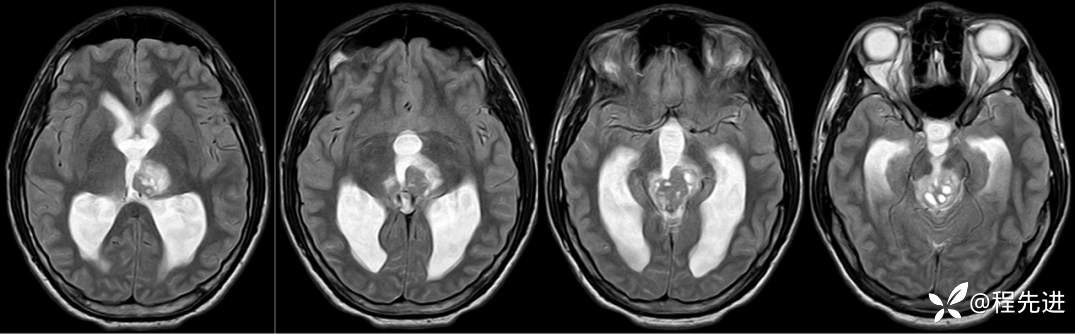

MRI平扫+增强:

T2: